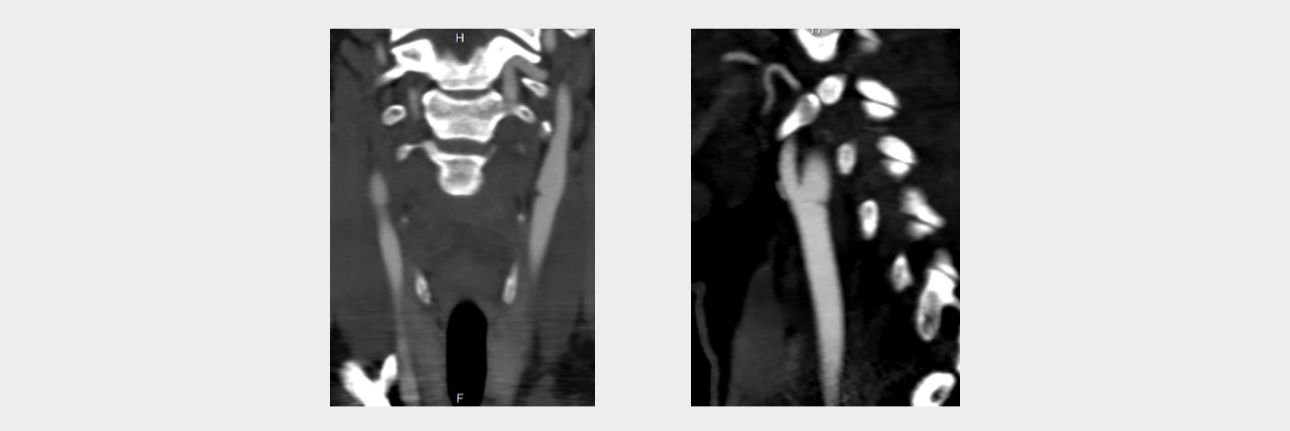

Computed tomography angiography

In order to clarify the changes detected on ultrasound, the patient underwent computed tomography (CT) angiography of extracranial arteries with intravenous contrast with Omnipack 350 in an amount of 50 ml on the SOMATOM Definition AS device (Siemens, Germany). According to the results of the study, linear structures were determined in the bifurcation of the common carotid artery on both sides, leading to a shelf-like defect in filling the vascular lumen in the sagittal scanning plane, more pronounced on the left (Fig. 5).

?

Conclusion: CT angiographic signs of the minimal variant of fibromuscular dysplasia (Carotid Web).

Computed tomography angiography

The results of the study confirmed the conclusion of ultrasound that the patient has a carotid network on both sides with a large stenosis on the left.